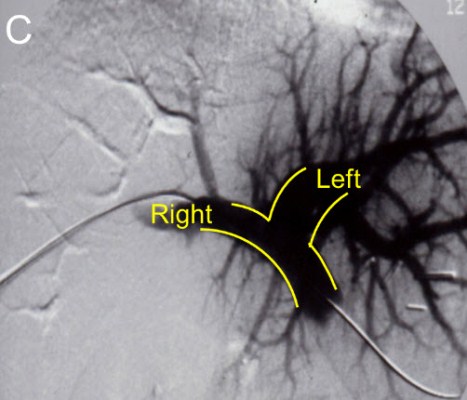

| (C) Loss of blood flow to the Right lobe of the liver after embolization |